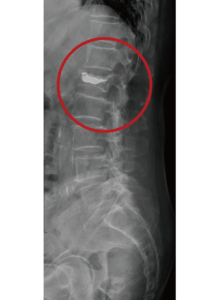

針對壓迫性骨折,X光的檢查是最基本的,尤其是一系列的X光記錄(比如每星期照一次做比對),可以發現脊椎的椎體變成楔狀(Wedge shape),也就是椎體的高度減少了,時間久一點甚至椎體裡還會出現空氣,就是告訴我們骨折沒有癒合,而且仍然處在不穩定的狀態。雖然X光可以診斷大多數的壓迫性骨折,但有些情況下,比如有很多節的壓迫性骨折,或病人疼痛已經持續一段時間,甚至是還有下肢麻痛的症狀,這些情況是需要利用核磁共振MRI來做進一步的檢查。

手術前               手術後

目前手術治療是以椎體成形術(Vertebroplasty)為主流,椎體成形術是在手術室裡利用X光機的導引,將椎體穿刺針插入椎體中,灌入骨水泥來支撐已經塌陷的椎體,有時還會利用水球或是俗稱千斤頂的椎體支架,來獲得更好的支撐效果。手術時間大概需要20分鐘,傷口小、安全、疼痛少、恢復迅速,是現在主要的治療方式。